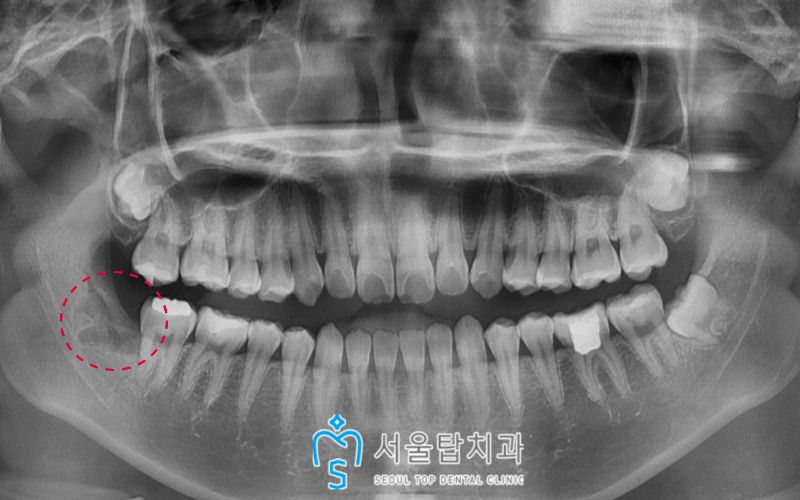

파노라마 사진을 촬영해 보았더니

오른쪽 아래 사랑니가

기울어진 상태로 맹출된 것을

확연히 체크 할 수 있었습니다.

그런데 발치를 진행하려고 하니,

사랑니가 아래턱 하방으로 지나가는

하치조 신경과 가까이 위치하는 것을

확인할 수 있었는데요..!